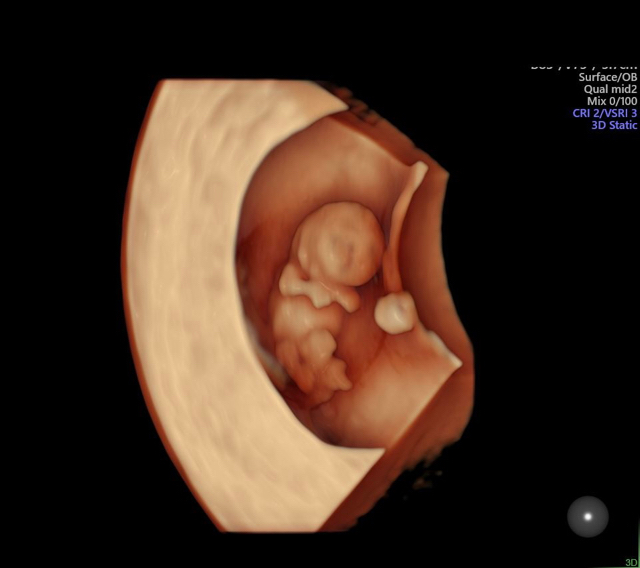

How’s baby looking? Is head okay?

Does it look like your babies? this is my rainbow after two looses..

My first baby had anencephaly (A Neural tube defect)